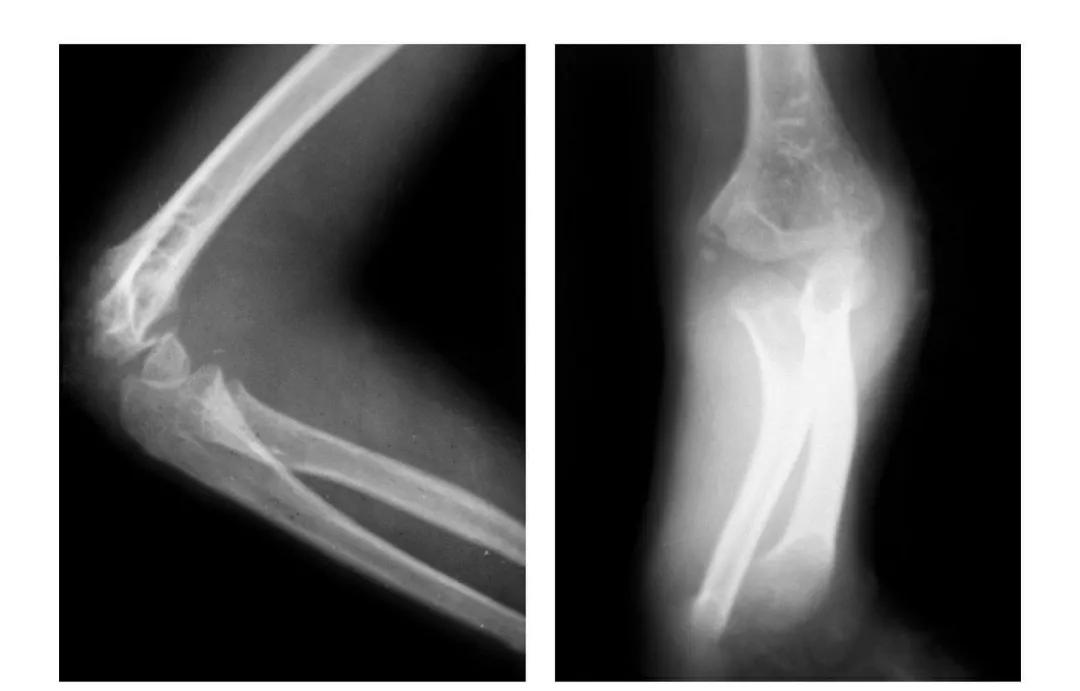

(二)部分骨折

本病亦称科-洛(Kocher-Lorenz)型骨折

例1:肱骨小头软骨面及其下方少量骨质呈“新月样”被剥脱,且向肘前上方移位并桡骨头前半部骨折。

例2:肱骨小头软骨面剥脱性骨折,致该小头新月状骨片被向前脱位的桡骨头顶向肘关节前上方,并尺骨干中段骨折(孟氏伸展型骨折)。